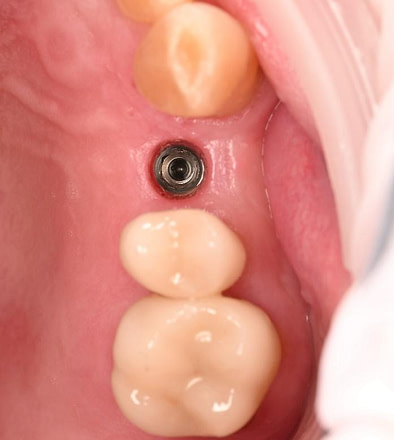

A custom surgical guide was designed and 3D printed, incorporating all the critical information from the virtual planning. The implant surgery was performed under local anesthesia, with the surgical guide firmly in place to ensure accurate implant placement. Bone grafting was performed to address the bony defect and promote optimal healing.

The Osstem OneGuide kit is used with a fully guided osteotomy and implant placement.

Osstem TSIII D4 x H10mm implant on NoMount driver.